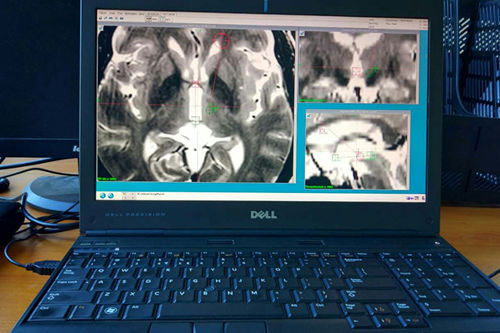

應(yīng)用先進(jìn)的手術(shù)計(jì)劃系統(tǒng):計(jì)算可精準(zhǔn)到0.1毫米的手術(shù)靶點(diǎn),路徑及入顱點(diǎn)

立體定向神經(jīng)外科手術(shù)(簡(jiǎn)稱腦立體定向術(shù)),在患者頭部安裝立體定向儀,行核磁檢查,應(yīng)用計(jì)算機(jī)技術(shù)及其軟件,把影像學(xué)資料傳輸至手術(shù)計(jì)劃系統(tǒng),進(jìn)行圖像的三維重建,可直觀顯示大腦的解剖結(jié)構(gòu),計(jì)算出手術(shù)靶點(diǎn)的精準(zhǔn)坐標(biāo)值,再輸入立體定向儀后進(jìn)行精準(zhǔn)手術(shù)。同時(shí)可設(shè)計(jì)手術(shù)穿刺路徑,計(jì)算病變大小和范圍,使手術(shù)個(gè)體化,到達(dá)更精準(zhǔn)、更安全、更有效、直觀、省時(shí)、創(chuàng)傷小的目的。目前在世界范圍應(yīng)用日益廣泛,分為二大類:1、腦深部核團(tuán)電刺激術(shù)或叫腦起博器(DBS)術(shù)。2,腦深部核團(tuán)切開術(shù)。